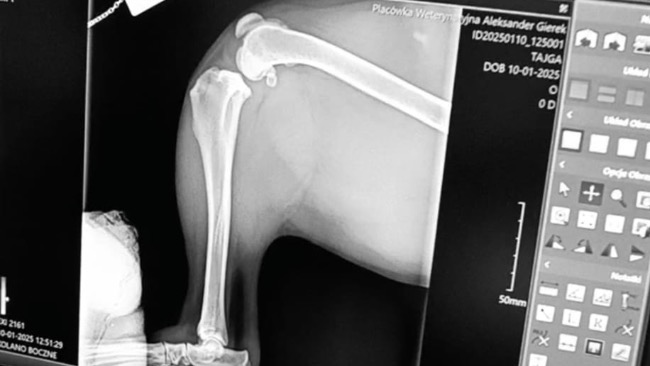

Cześć, nazywam się Krystian i wraz z moją córką zwracamy się do Was z ogromną prośbą o pomoc dla naszej ukochanej suczki Tajgi. Tajga ma 4 lata i zawsze była pełna życia, energii i miłości. Niestety, ostatnio spotkało ją wielkie nieszczęście – zerwała więzadło w tylnej łapie, przez co nie może chodzić a jeśli już to z wielkim bólem i trudem. Widok jej smutku i cierpienia łamie nam serca, bo Tajga jest dla nas członkiem rodziny, który zawsze dawał nam radość i wsparcie.